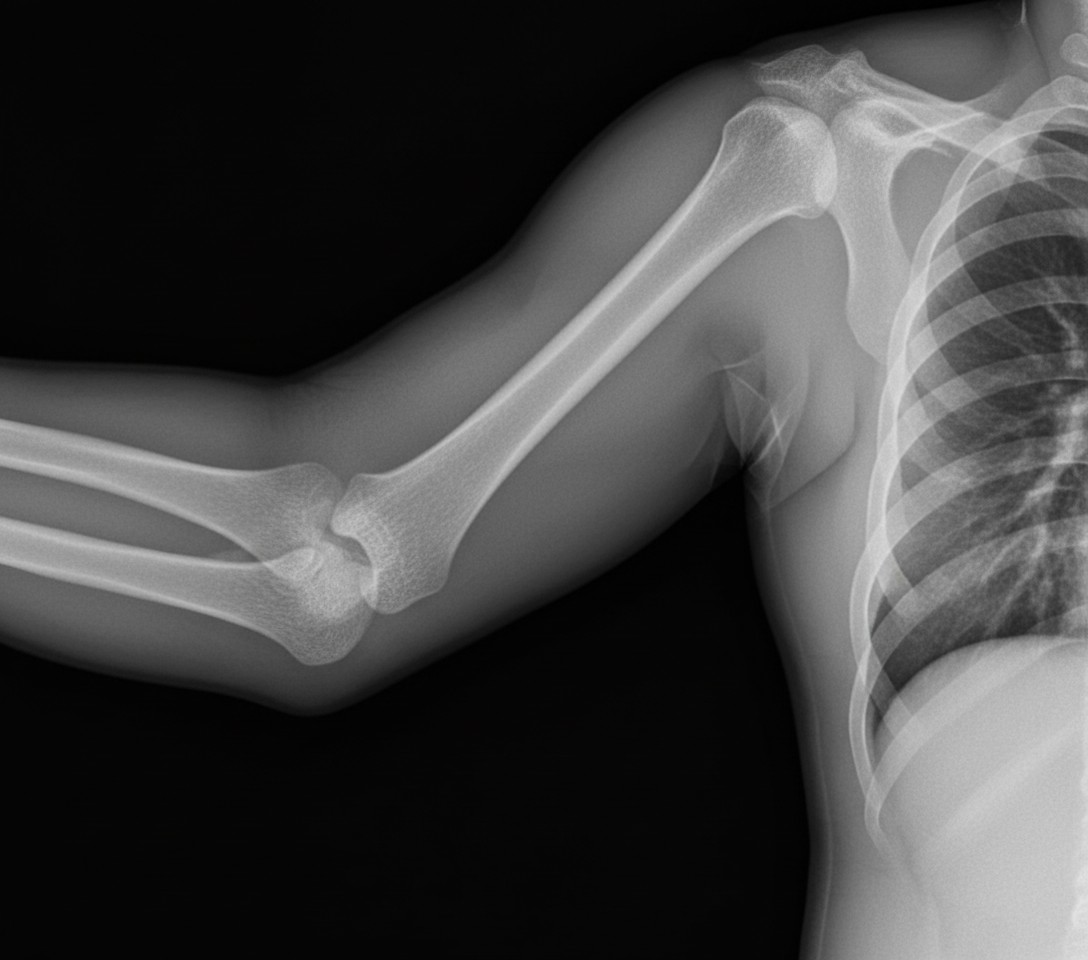

An 18-year-old male presents with a history of trauma. An X-ray is shown below. What is the diagnosis?

Explanation: ***Monteggia fracture*** - Characterized by a **proximal ulna fracture** with **radial head dislocation**, which fits the typical pattern seen in trauma cases involving the forearm. - The **radiocapitellar line** on X-ray fails to pass through the center of the capitellum, confirming radial head dislocation - a pathognomonic sign. *Supra-Condylar Fracture* - Occurs in the **distal humerus** above the condyles, most commonly in children aged 5-8 years. - Would show **posterior angulation** of the distal fragment and potential **anterior humeral line** disruption on lateral X-ray. *Colles' Fracture* - Involves the **distal radius** with **dorsal displacement** and angulation, creating a "dinner fork" deformity. - Typically occurs in **elderly patients** following a fall on an outstretched hand, not involving ulna or radial head. *Galeazzi fracture* - Features a **distal radius fracture** with **distal radioulnar joint (DRUJ) dislocation**, opposite to Monteggia pattern. - Mnemonic: **"GRU"** - Galeazzi = Radius fracture + Ulnar dislocation; **"MoRU"** - Monteggia = Radius dislocation + Ulnar fracture.